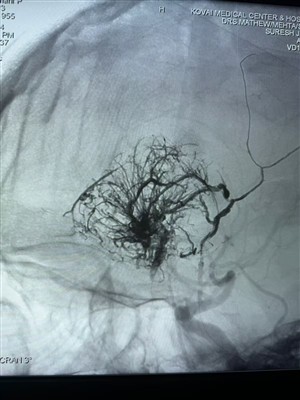

Adroddwyd am yr Achos Cyntaf o Diwmor Gorfasgwlaidd yn IndiaHapus i rannu'r achos tiwmor hyperfasgwlaidd cyntaf hwn a berfformiwyd yn India. Cafodd ei drin â System Embolig Hylif Lafa gan NeuroSafe Medical Co., Ltd. Diolch i Dr. Mathew Cherian. Arloesodd ym...

Achos AVM Newydd Defnyddiodd Asiant Embolig Hylif LavaRhannwch achos AVM newydd a ddefnyddir Asiant Embolig Hylif Lava o Neurosafe Medical Co., Ltd. Mae'r ddelwedd fel a ganlyn: